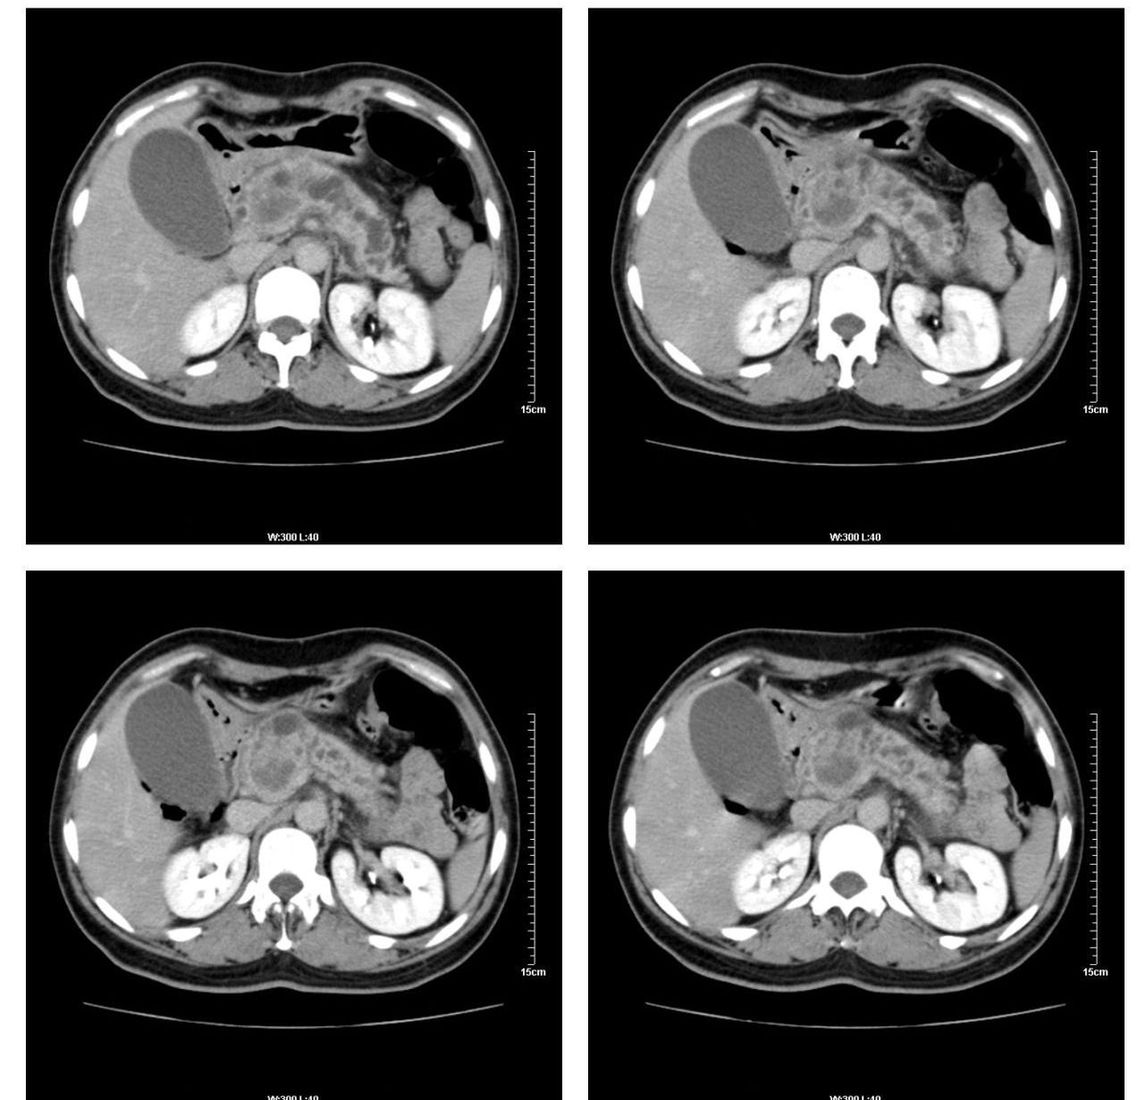

标题: CT13800:女性,52岁。腹痛、腹胀、消瘦及乏力5个月。 [打印本页]

标题: CT13800:女性,52岁。腹痛、腹胀、消瘦及乏力5个月。

慢性胰腺炎、胰腺假囊肿形成,胆总管梗阻,胆囊扩张

胰腺癌可能大

考虑胰头癌

考虑胰腺囊腺癌。

考虑胰头癌可能。

各期时间抓的不太好,门静脉始终显示不佳(门脉瘤栓形成?)。